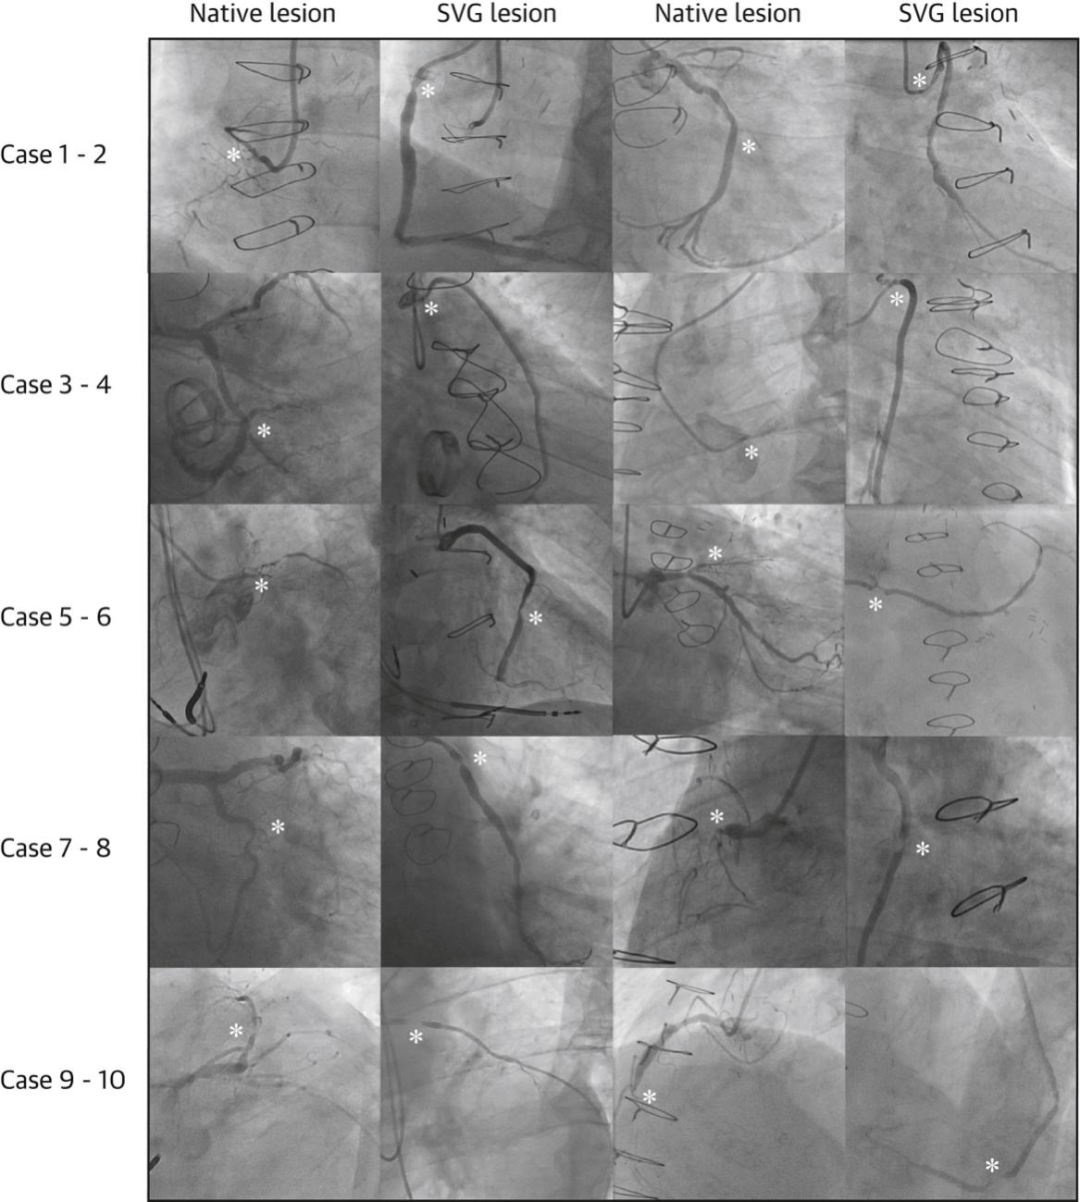

前10例连续病例原生血管病变和静脉桥病变造影图

这样的筛选标准使试验人群相对稳定,避免早期桥血管急性失功或高风险SVG病变干扰结果。患者被1:1随机分配接受SVG-PCI或原生冠脉PCI治疗。所有患者均使用第二代药物洗脱支架完成干预。